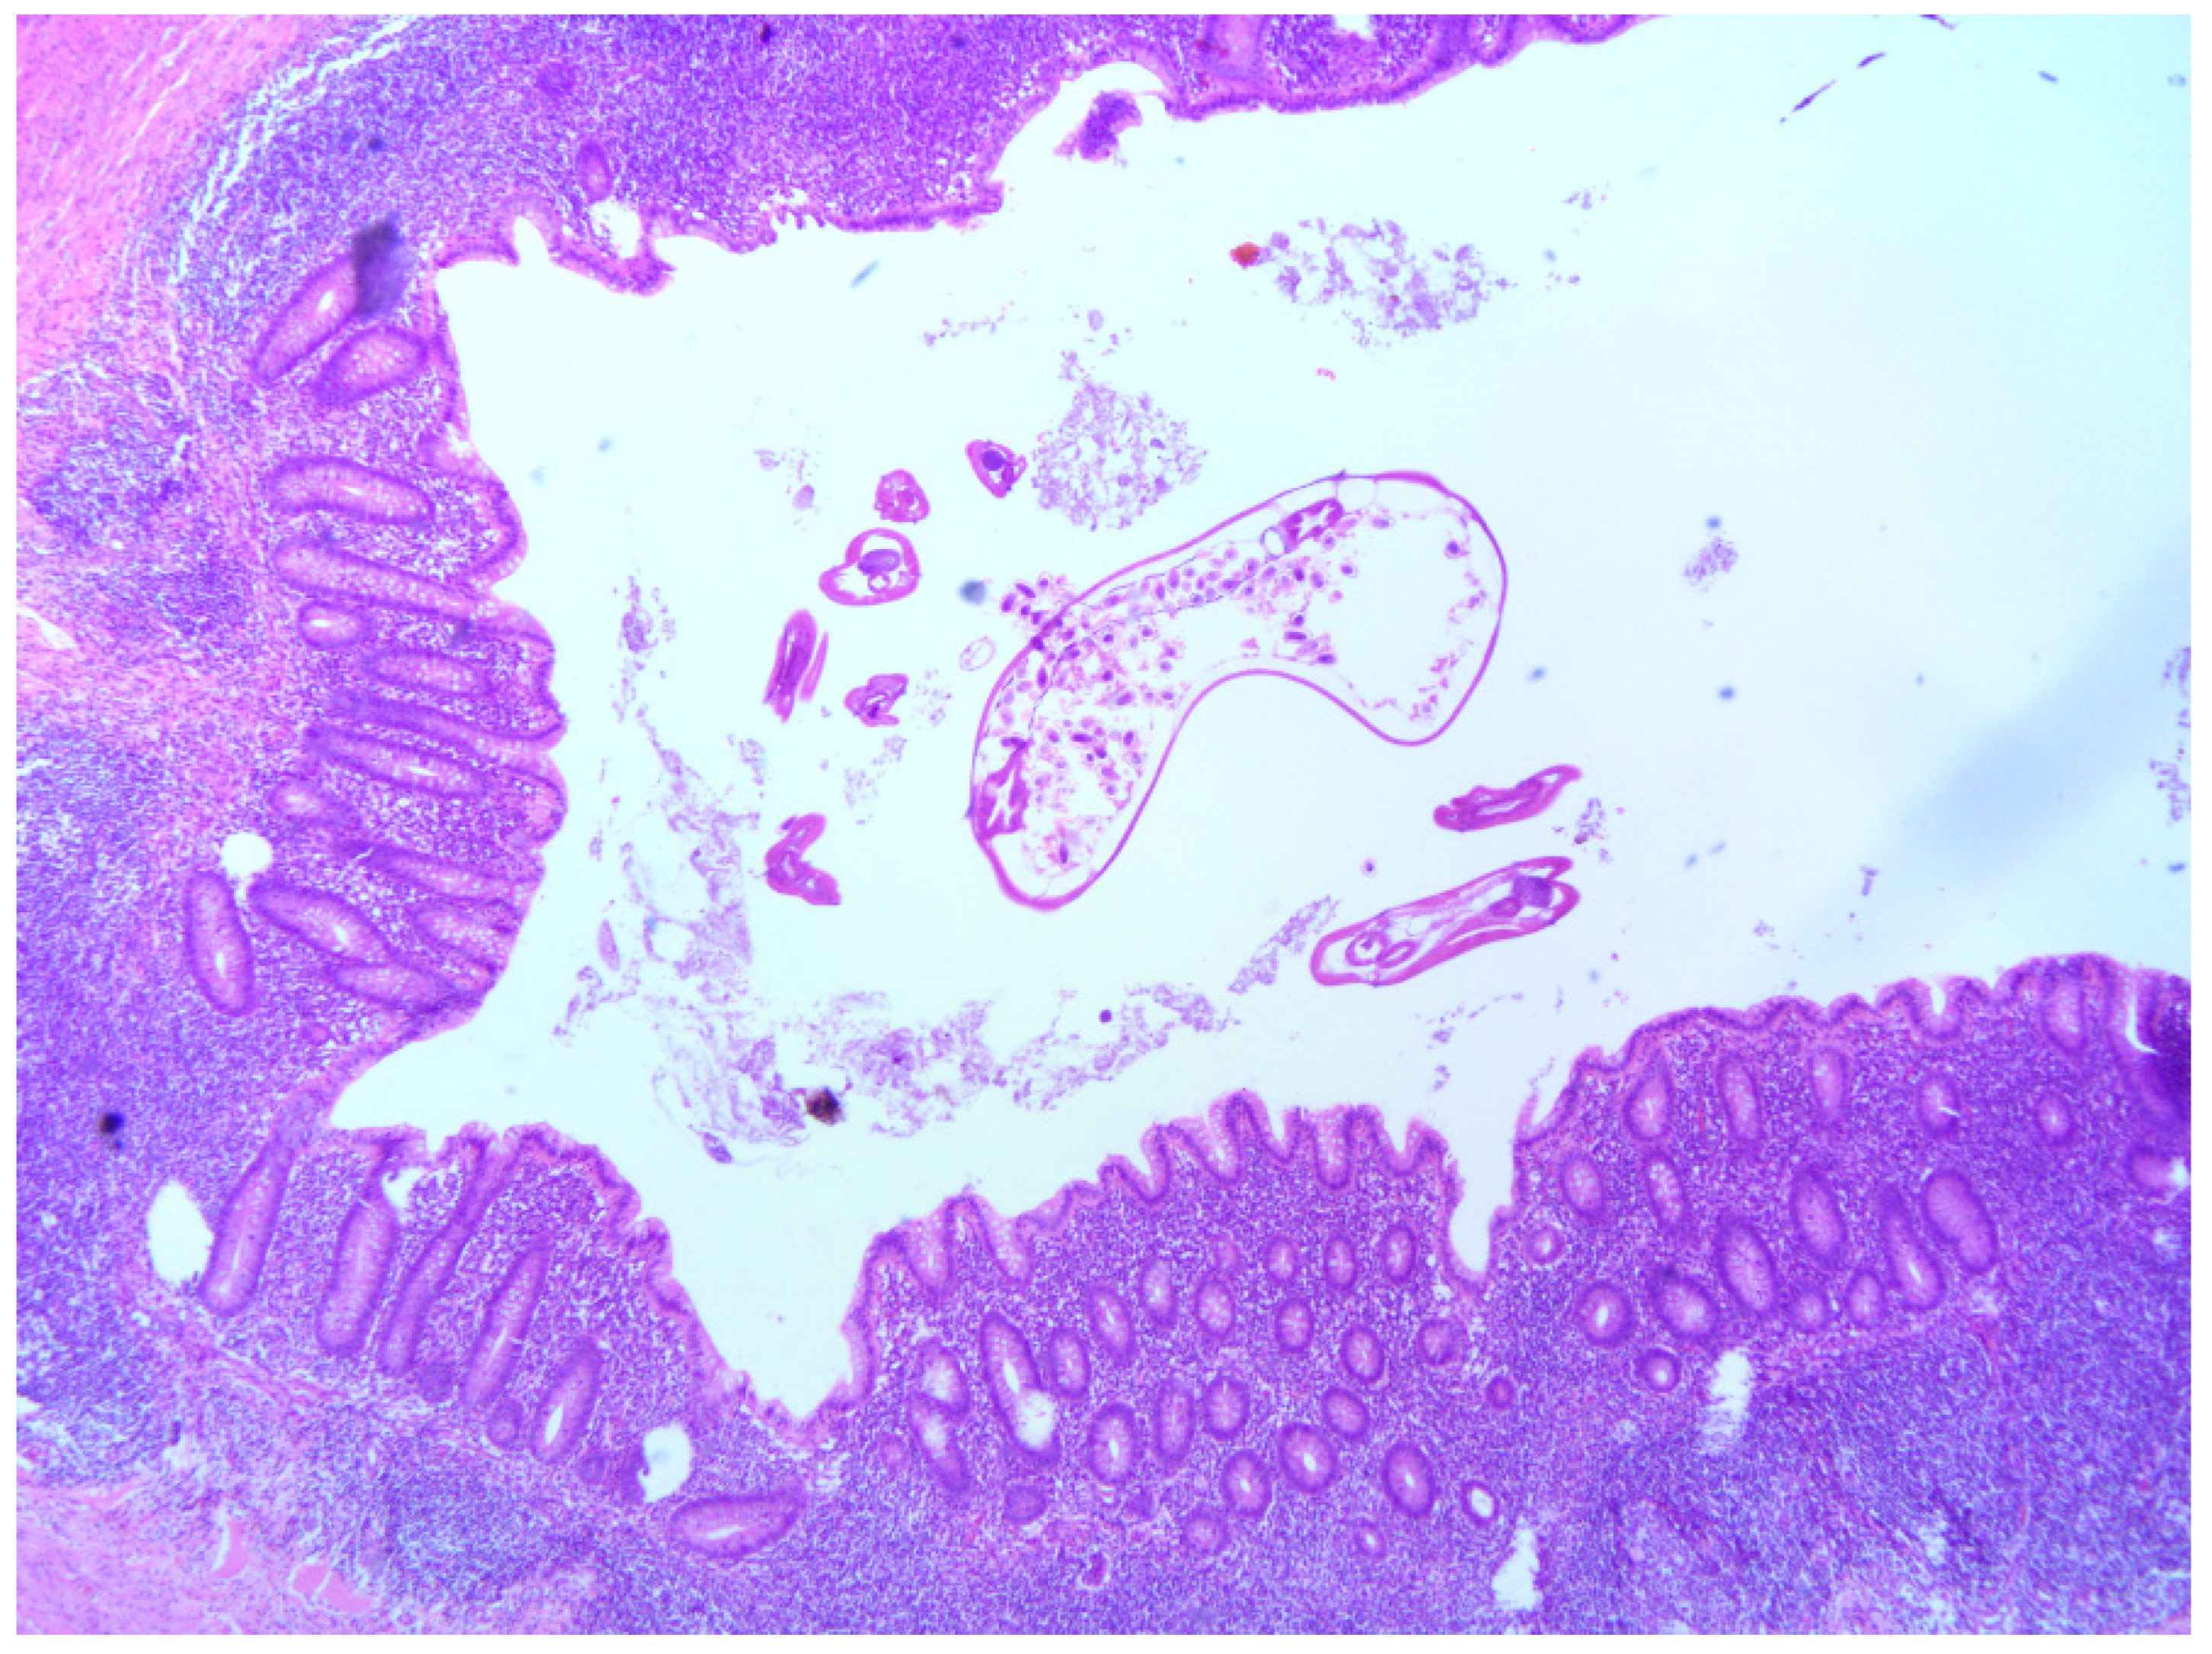

Figure 2.

Acute appendicitis with luminal Enterobius vermicularis in a 13-year-old girl, HE, 4×. Neutrophilic infiltration in all layers of the appendix wall with Enterobius vermicularis in the lumen of the appendix.